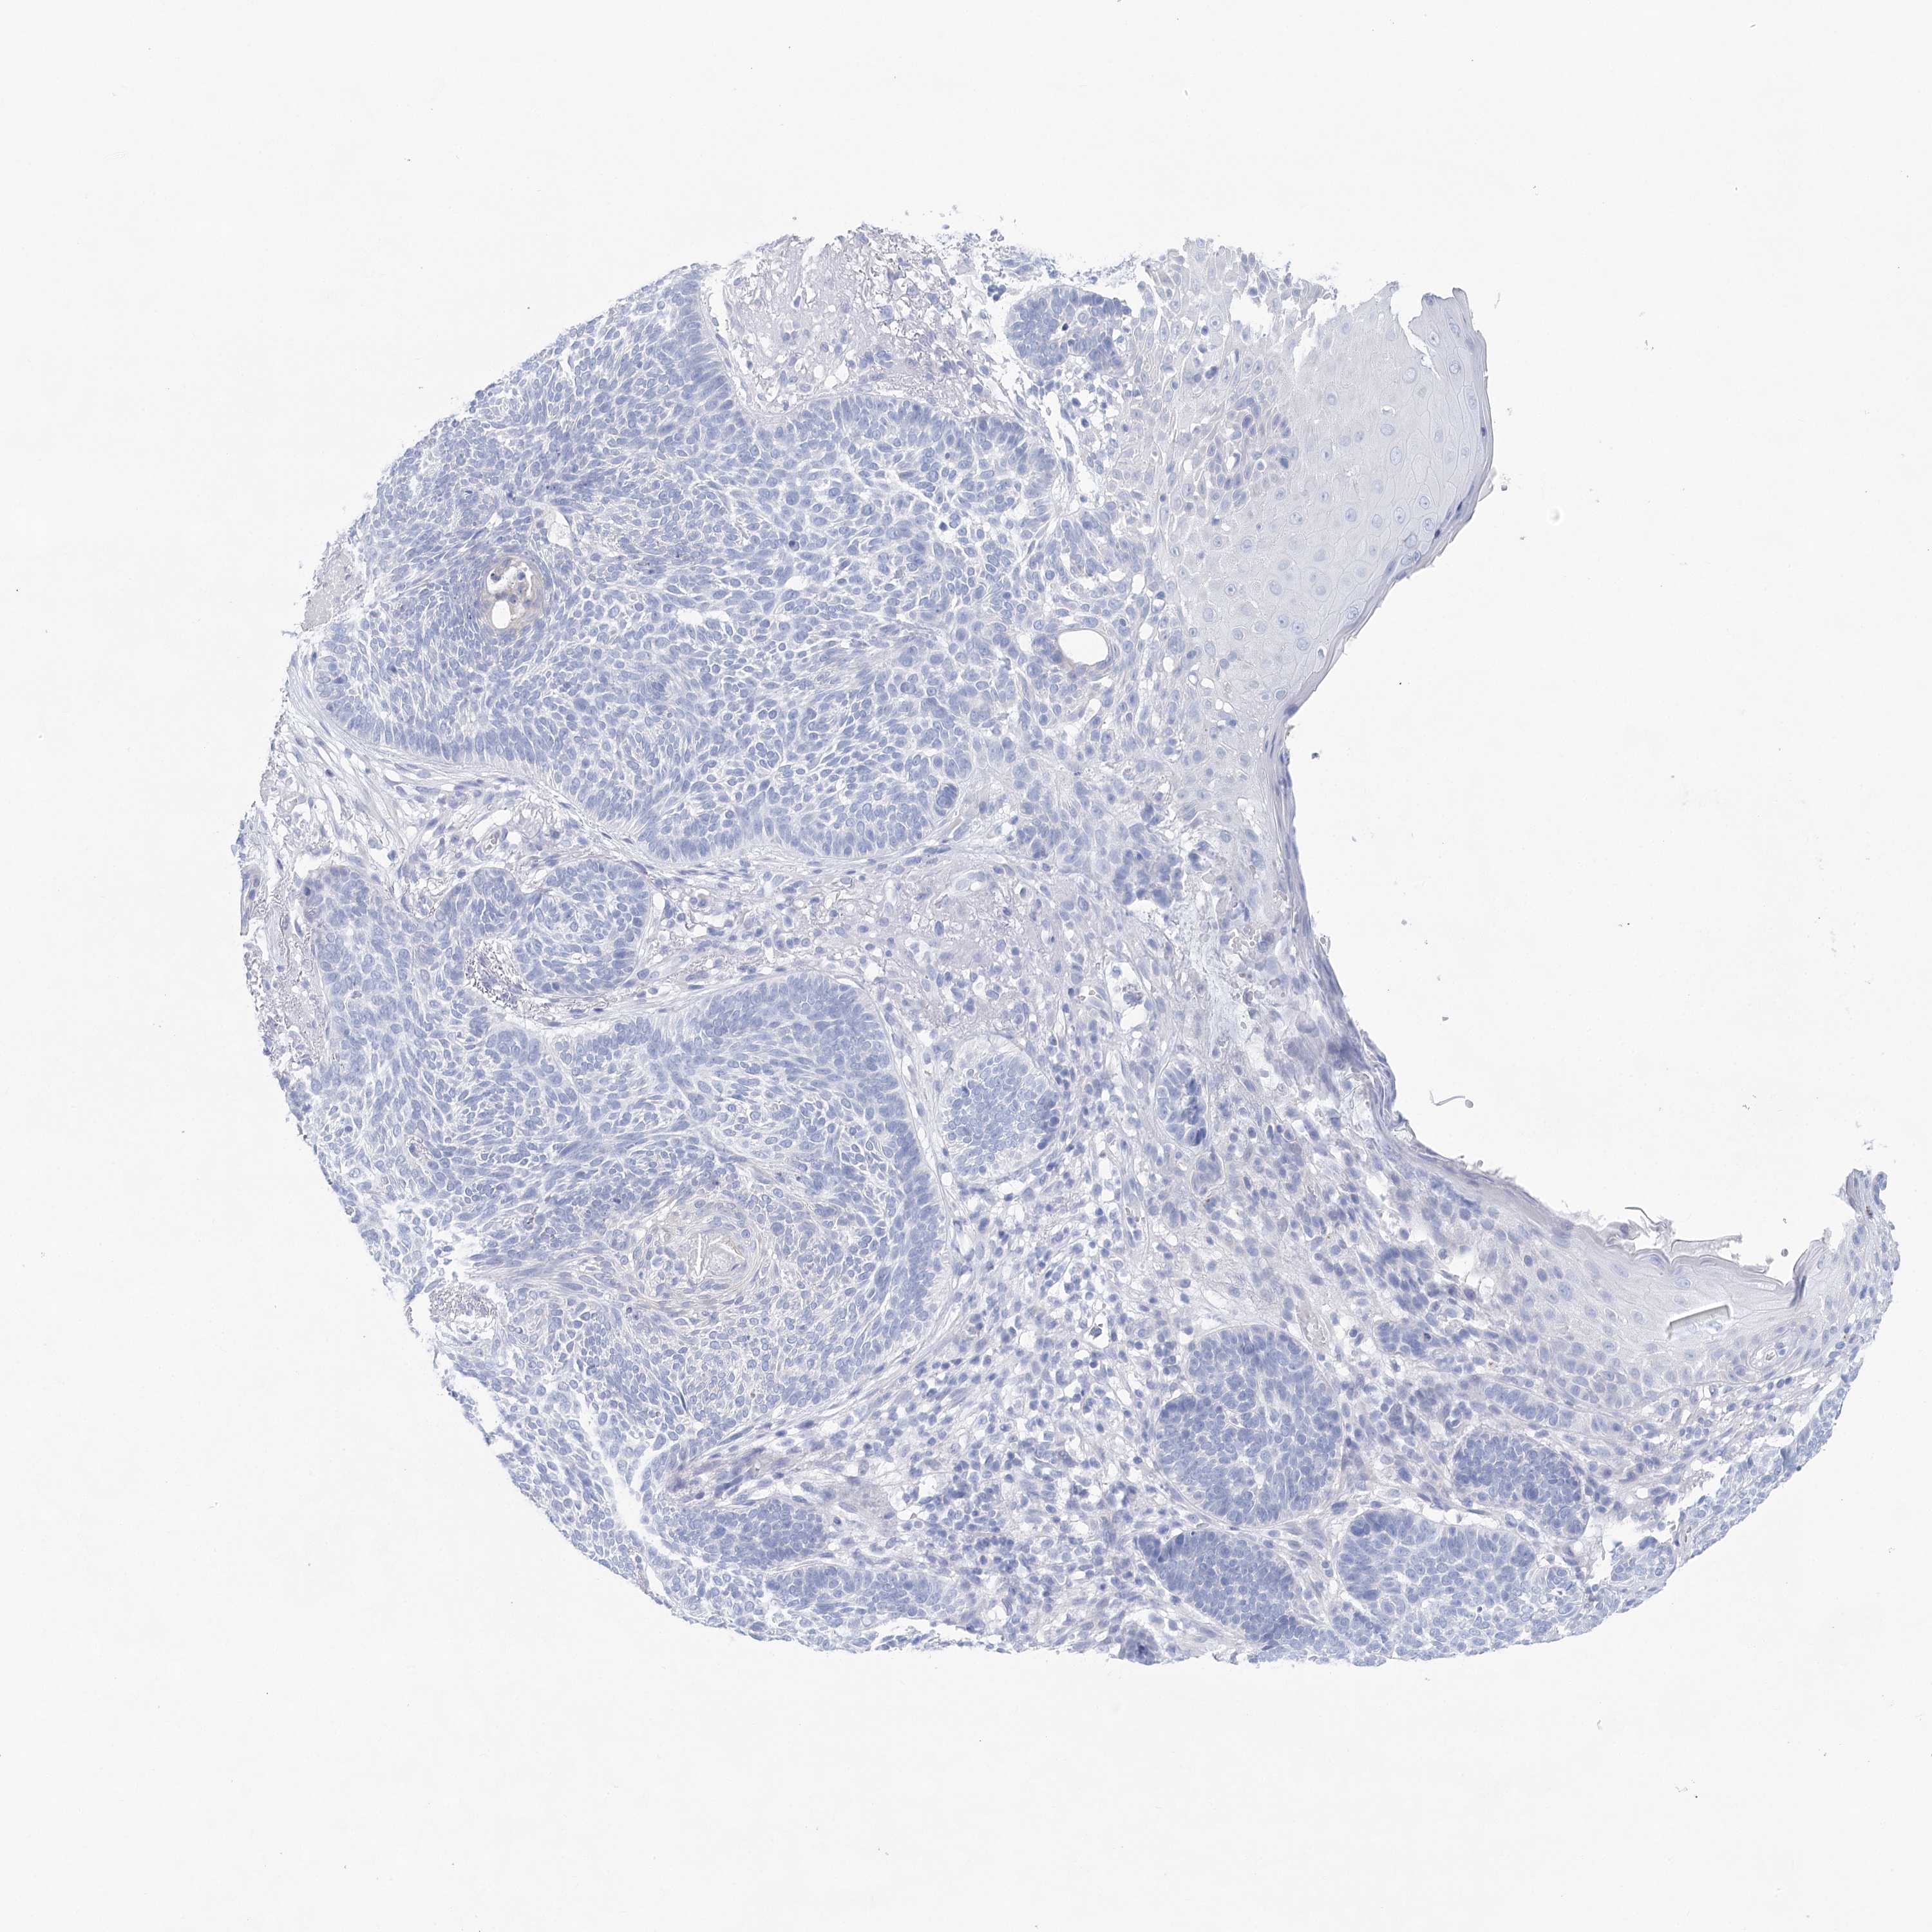

CANCER SKIN CANCER Show tissue menu

Basal cell and squamous cell cancer

SKIN CANCER - Protein expressioni

A mouse-over function shows sample information and annotation data. Click on an image to view it in a full screen mode. Samples can be filtered based on level of antibody staining by selecting one or several of the following categories: high, medium, low and not detected. The assay and annotation is described here.

Each image is clickable and will lead to virtual microscopy that enables deeper exploration of all samples and also displays staining intensity scores, fraction scores and subcellular localization as well as patient and tissue information for each sample.

Antibody HPA029855

Antibody HPA029856

Antibody CAB026343

Basal cell carcinoma

Squamous cell carcinoma, NOS

Squamous cell carcinoma, metastatic, NOS